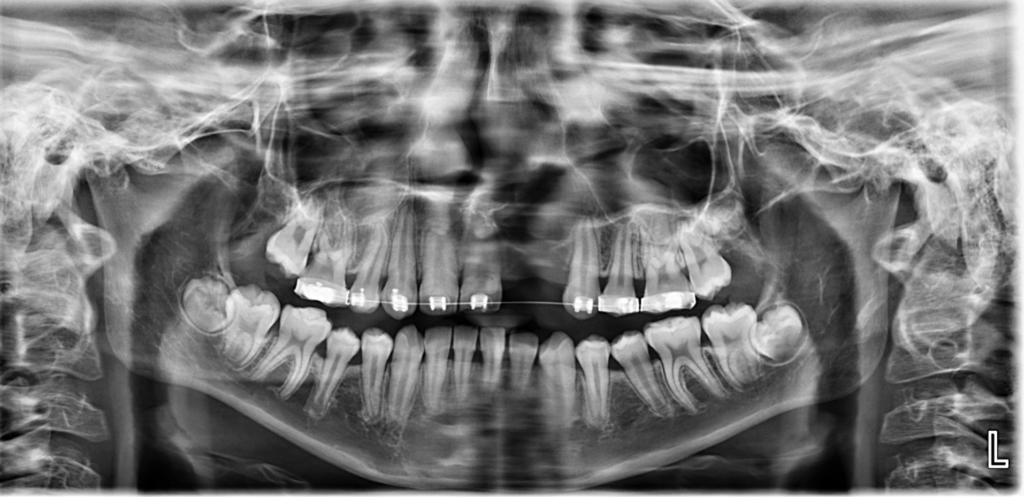

Paciente masculino de 15 años de edad acude al Instituto de Diagnóstico Maxilofacial – IDM para evaluación imagenológica por motivos ortodónticos.

En la radiografía panorámica (Figura 1), se observa neumatización de senos maxilares, defecto óseo en zona anterior izquierda de maxilar superior, ausencia de piezas 22 y 23; además de la aparatología ortodóntica en piezas del maxilar superior.

Radiografia Panorámica